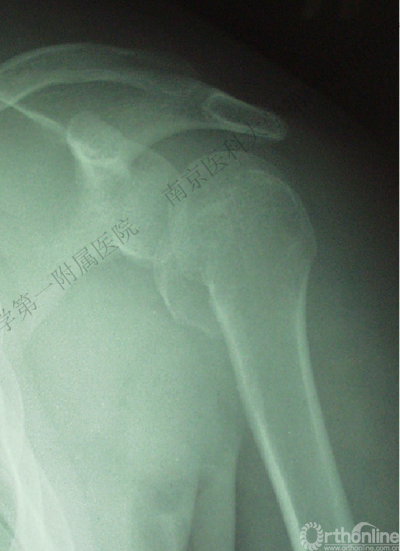

男性,40岁,摔伤后右肩关节肿痛、活动受限2天。

术后肩关节X线正位片

1.X线片